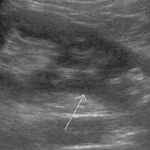

2-Kidney hump

تسمى أيضا Dromedary hump وهي مثل البروز في شكل parenchyma الكلية كسنام الجمل. سماكتها يجب أن تتناسق مع بقية parenchyma المحيطة بدون بروز. هي شائعة تحديدا في الكلية اليسرى وذلك لأن التغير يحدث في مرحلة تطور الجنين وضغط الطحال على الكلية.

في هذه الحالات يجب التأكد من السماكة (متناسقة) و echogenicity (غير مختلفة) و colour Doppler (طبيعية).